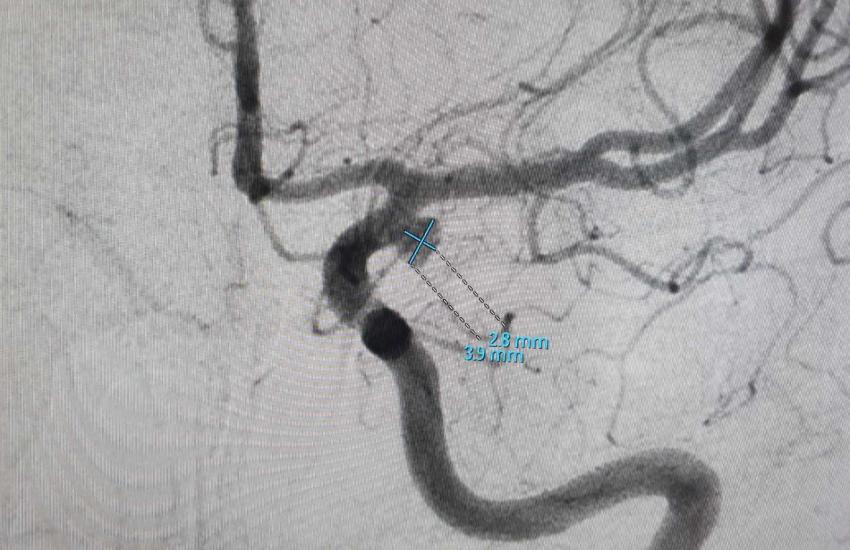

14 серпня у відділенні інтервенційної радіології сумісними зусиллями лікарів Черкаської обласної лікарні за участю завідувача нейрохірургічного відділення КП «Полтавська обласна клінічна лікарня ім. М.В. Скліфосовського Полтавської обласної ради» Тончева Михайла Дмитровича та за підтримки компаній Medtronic проведена операція ендоваскулярне виключення (мікроспіралізація) аневризми лівої внутрішньої сонної артерії. Унікальність операції в тому, що хірурги провели складні маніпуляції з артеріями головного мозку через невеликий прокол у паху, а не вдалися до трепанації черепа. Операція тривала біля години, пройшла успішно та з мінімальною крововтратою (приблизно 10 мл). Наразі пацієнтка залишається під пильним наглядом лікарів в КНП «Черкаська обласна лікарні Черкаської обласної ради» та продовжує лікування.